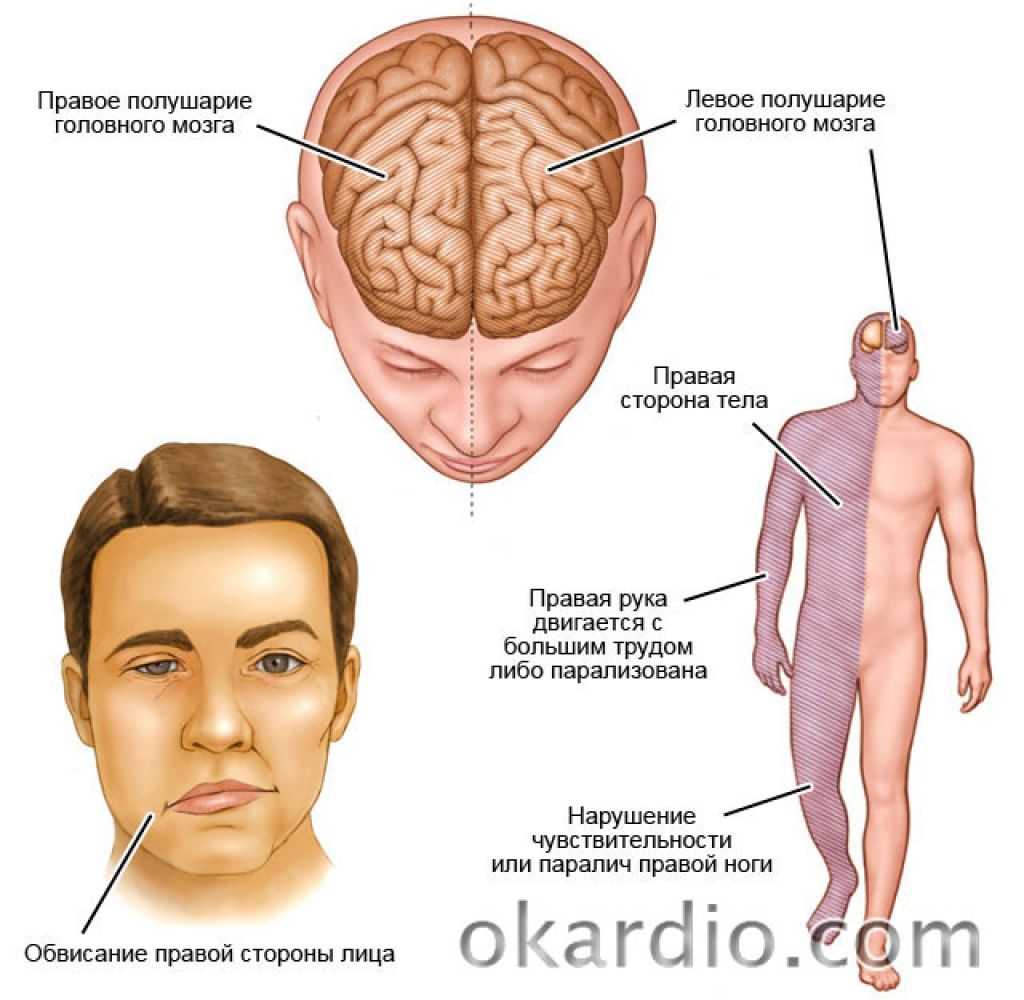

Ишемический инсульт левой стороны: симптомы и реабилитация